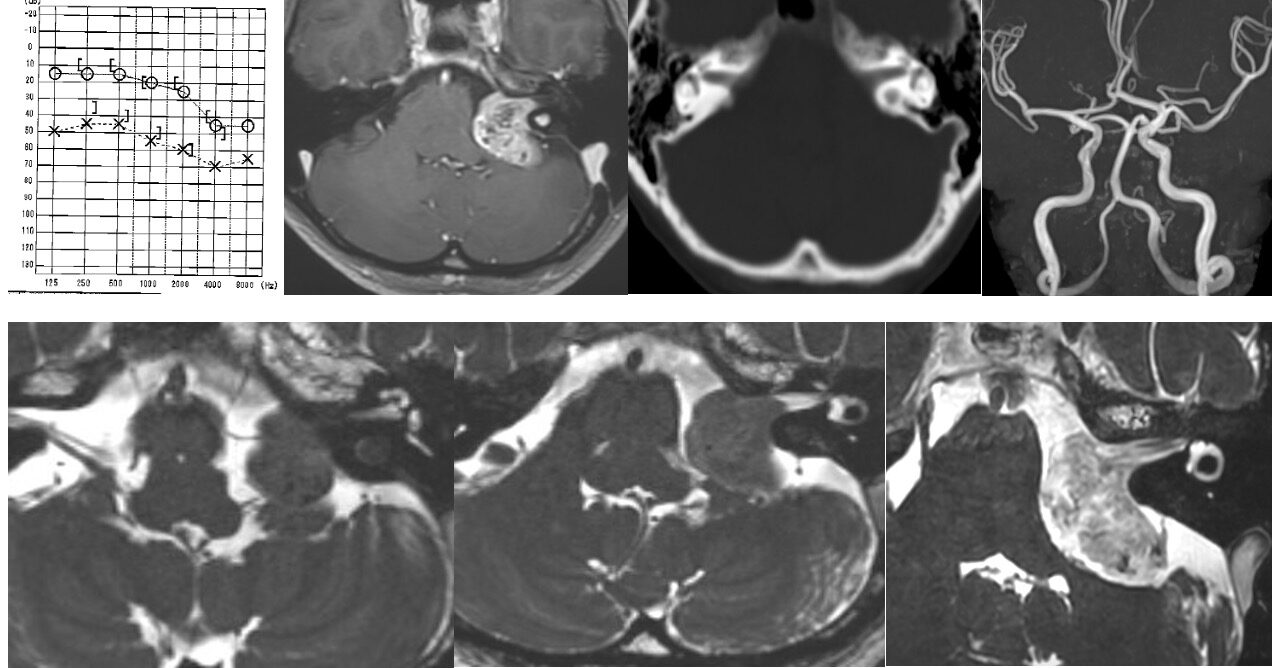

外頸動脈から腫瘍濃染が認められていたため、ある程度の出血は予想して手術に入りましたがそれ以上でした。内減圧が出血でなかなか進みません。腫瘍を硬膜から剥がすと主要表面からも動脈性出血が起こり、止血に難渋しました。腫瘍表面を凝固操作しているうちに、手術の最終段階で顔面神経はしっかり確認できるが電気的反応がなくなりました。手術が長時間かかった関係で小脳が挫傷となって腫れてしまい、救命のため小脳を一部切除してようやく手術を終えることができました。術後、小脳失調、顔面神経麻痺が出現し、術後1週間程度は意識も悪かったです。幸い術後3週間目から急速に回復され、食事や補助歩行が可能となりました。顔面神経のENoGの反応も残っており、回復が期待できます。現在リハビリ中です。これまで最大級の難敵でしたが、無事に生還してよかったです。